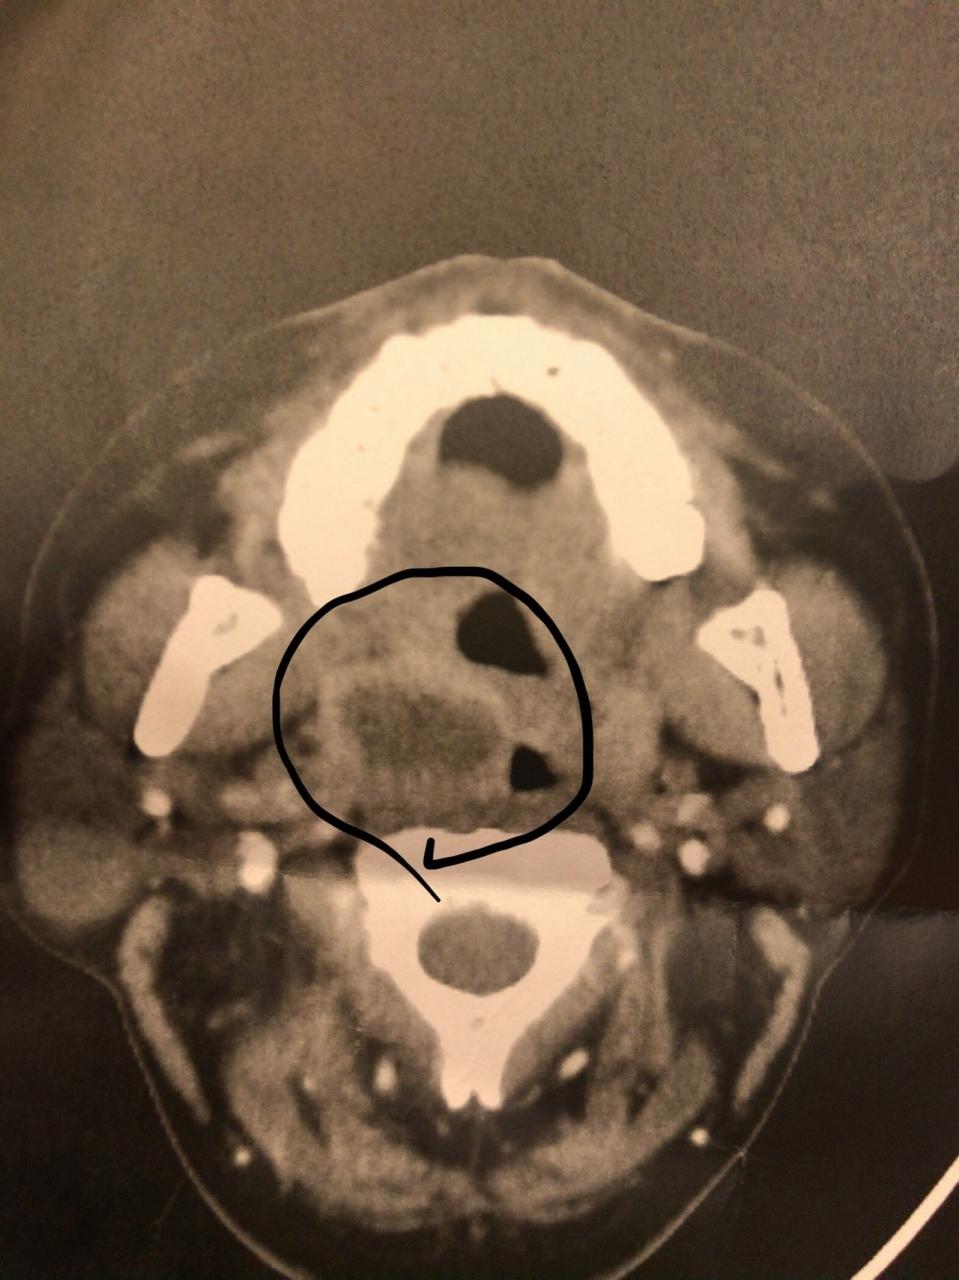

• しかし3月の後半から喉の痛みに襲われ、病院で薬もらうも治らなくて、3月31日の夜に急患センターに行くと「紹介状書くからすぐに近くの総合病院の急患外来に行ってください」と言われ、そこで受診してもらうと、扁桃腺に膿が溜まる扁桃周囲膿瘍という病気でそのまま入院することに。<br /><br />1週間は入院とのことで18000円のいい席とったのに泣く泣くライブは諦めてホテルをキャンセルしました。<br />

しかし3月の後半から喉の痛みに襲われ、病院で薬もらうも治らなくて、3月31日の夜に急患センターに行くと「紹介状書くからすぐに近くの総合病院の急患外来に行ってください」と言われ、そこで受診してもらうと、扁桃腺に膿が溜まる扁桃周囲膿瘍という病気でそのまま入院することに。

1週間は入院とのことで18000円のいい席とったのに泣く泣くライブは諦めてホテルをキャンセルしました。

• そこからずーっと点滴の毎日。<br />1日3回の抗生剤と食事とれてない分の栄養や水分の何かしらの点滴が24時間ずっと。<br /><br />そしたら経過が良かったらしく、ライブ当日の午前中に退院できることになり、迷った結果、やっぱりチケット代が勿体ないってことでバタバタ用意して行くことに。<br /><br />幸い喉が悪いだけなので、ほぼ動いてなくて体力と筋力は多少落ちてたけど、体動かすのは問題なかったので。<br /><br />ホテルもすぐに確保できました。

そこからずーっと点滴の毎日。

1日3回の抗生剤と食事とれてない分の栄養や水分の何かしらの点滴が24時間ずっと。